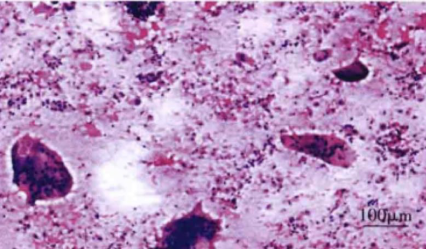

8. 甲状腺活检:滤泡破坏和炎症细胞浸润伴肉芽肿形成是本病的病理特征。

低倍镜下标本中的多核巨细胞、周围包绕大量炎症细胞碎片(涂片,HE 染色)

图片来源:甲状腺疾病超声诊断图谱